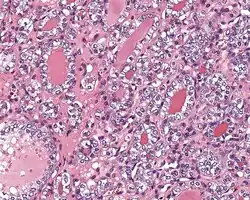

Histopathology of NIFTP, H&E stain.[1]

1. ^ Image by Mikael Häggström, MD. Reference for findings: Rachel Jug, M.B.B.Ch., B.A.O., David Poller, M.D., Xiaoyin "Sara" Jiang, M.D. "NIFTP". Pathology Outlines.{{cite web}}: CS1 maint: multiple names: authors list (link) Last author update: 10 May 2018